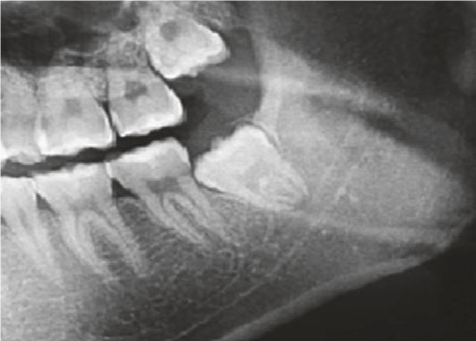

Jei protiniams dantims nėra galimybės tinkamai išdygti, nustatomas dantų susigrūdimas – tokia situacija yra ganėtinai pavojinga, nes susigrūdę dantys gali sukelti infekciją, lemti gretutinių dantų gedimą, dantenų ligas ar cistų formavimąsi. Kai siekiama išvengti šių problemų, odontologai rekomenduoja protinius dantis pašalinti. Prieš tai yra atliekama rentgeno nuotrauka, kuri padeda nustatyti dantų rovimo būtinybę.

Taip yra yra vadinami įstrigę arba nedygstantys protiniai dantys, kurie gali būti visiškai susiformavę, tačiau taip ir neišdygę. Odontologai skiria du pagrindinius protinių dantų retencijos laipsnius: